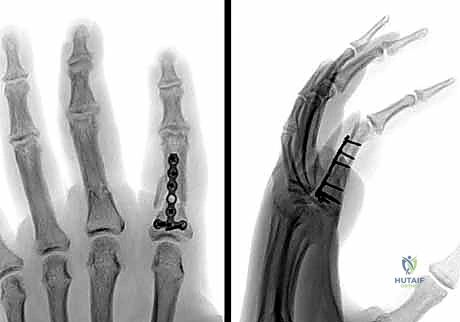

في الكسور المفتتة أو المعقدة، يقوم الدكتور هطيف بعمل شق جراحي دقيق (غالباً من الجانب لتجنب الأوتار الظهرية) لكشف الكسر وإعادة ترتيب الشظايا العظمية بدقة متناهية، ثم تثبيتها باستخدام:

* البراغي الساحبة (Lag Screws): تُستخدم في الكسور المائلة الطويلة أو الحلزونية لتوفير ضغط قوي بين حواف الكسر.

* الصفائح والبراغي الدقيقة (Mini-plates and Screws): تُستخدم في الكسور العرضية أو المفتتة لتوفير تثبيت صلب وقوي يسمح بحركة الإصبع في اليوم التالي للعملية.